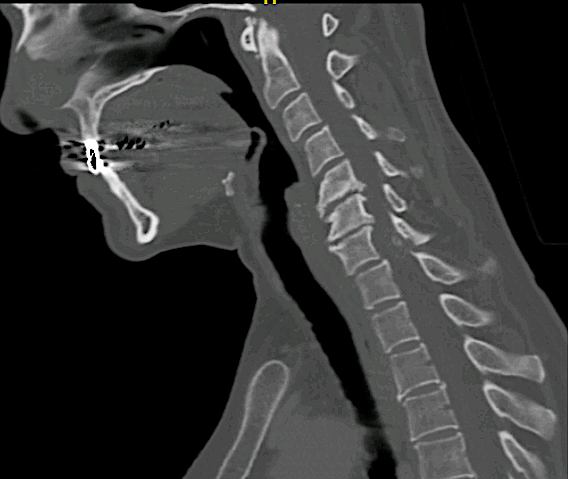

La lesión se ubicaba en el margen anterior de la lámina sin aparente afectación ósea en la RM cervical.

Se solicitó un TC observando signos de espondilosis avanzada C5-C6-C7 y ausencia de infiltración ósea.

En la imagen coronal se aprecia relación íntima de la lesión con la faceta C7-Th1 que nos hizo sospechar el diagnóstic